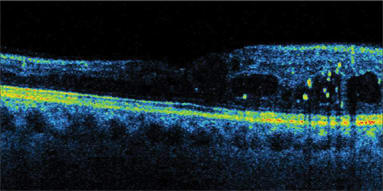

Angioid streaks with CNV. |

Lamellar hole. |

CME post-traumatic injury. |

Proliferative diabetic retinopathy. |